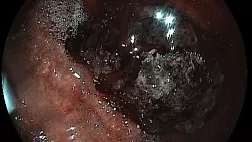

Клинические случаи: Эозинофильный эзофагит

эозинофильный_эзофагит_EndoExpert.ru.png